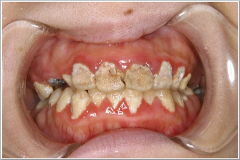

その後、更に症状が悪化し、ついに入浴、歯磨き、更衣が出来なくなってしまいました。その後、体の不調や歯痛に耐え、当クリニックを訪れたのは、歯磨きが出来なくなって七年目の春でした。その時のお口の中の状態です。

歯がプラークにすっかり包まれ、前歯はむし歯で溶かされ、歯ぐきは炎症で真っ赤に腫れ上がっています。プラークの染め出し液を使えば歯全体が真っ赤に染まって、汚れの具合がよく分かるのですが、あまりいやな思いはさせられませんので止めました。